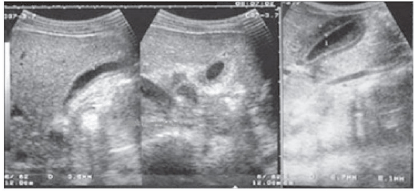

A febre do dengue hemorrágico (FDH) é uma arbovirose responsável por epidemias anuais no Brasil. Sua principal característica é o aumento da permeabilidade capilar, representada pela fuga de líquido e albumina para o espaço extravascular, levando a derrames cavitários e hemoconcentração com elevação do hematócrito, descrita como polisserosite, classificada em formas leves e graves, segundo critérios da Organização Mundial da Saúde. Embora os achados à ultrassonografia sejam inespecíficos, o método contribui para o diagnóstico precoce em pacientes com FHD e no diagnóstico diferencial de outras doenças febris.

Considerando as informações abaixo, assinale a alternativa correta quanto a principal hipótese diagnóstica da imagem ultrassonográfica apresentada.

Considerando as informações abaixo, assinale a alternativa correta quanto à principal hipótese diagnóstica da imagem ultrassonográfica apresentada.